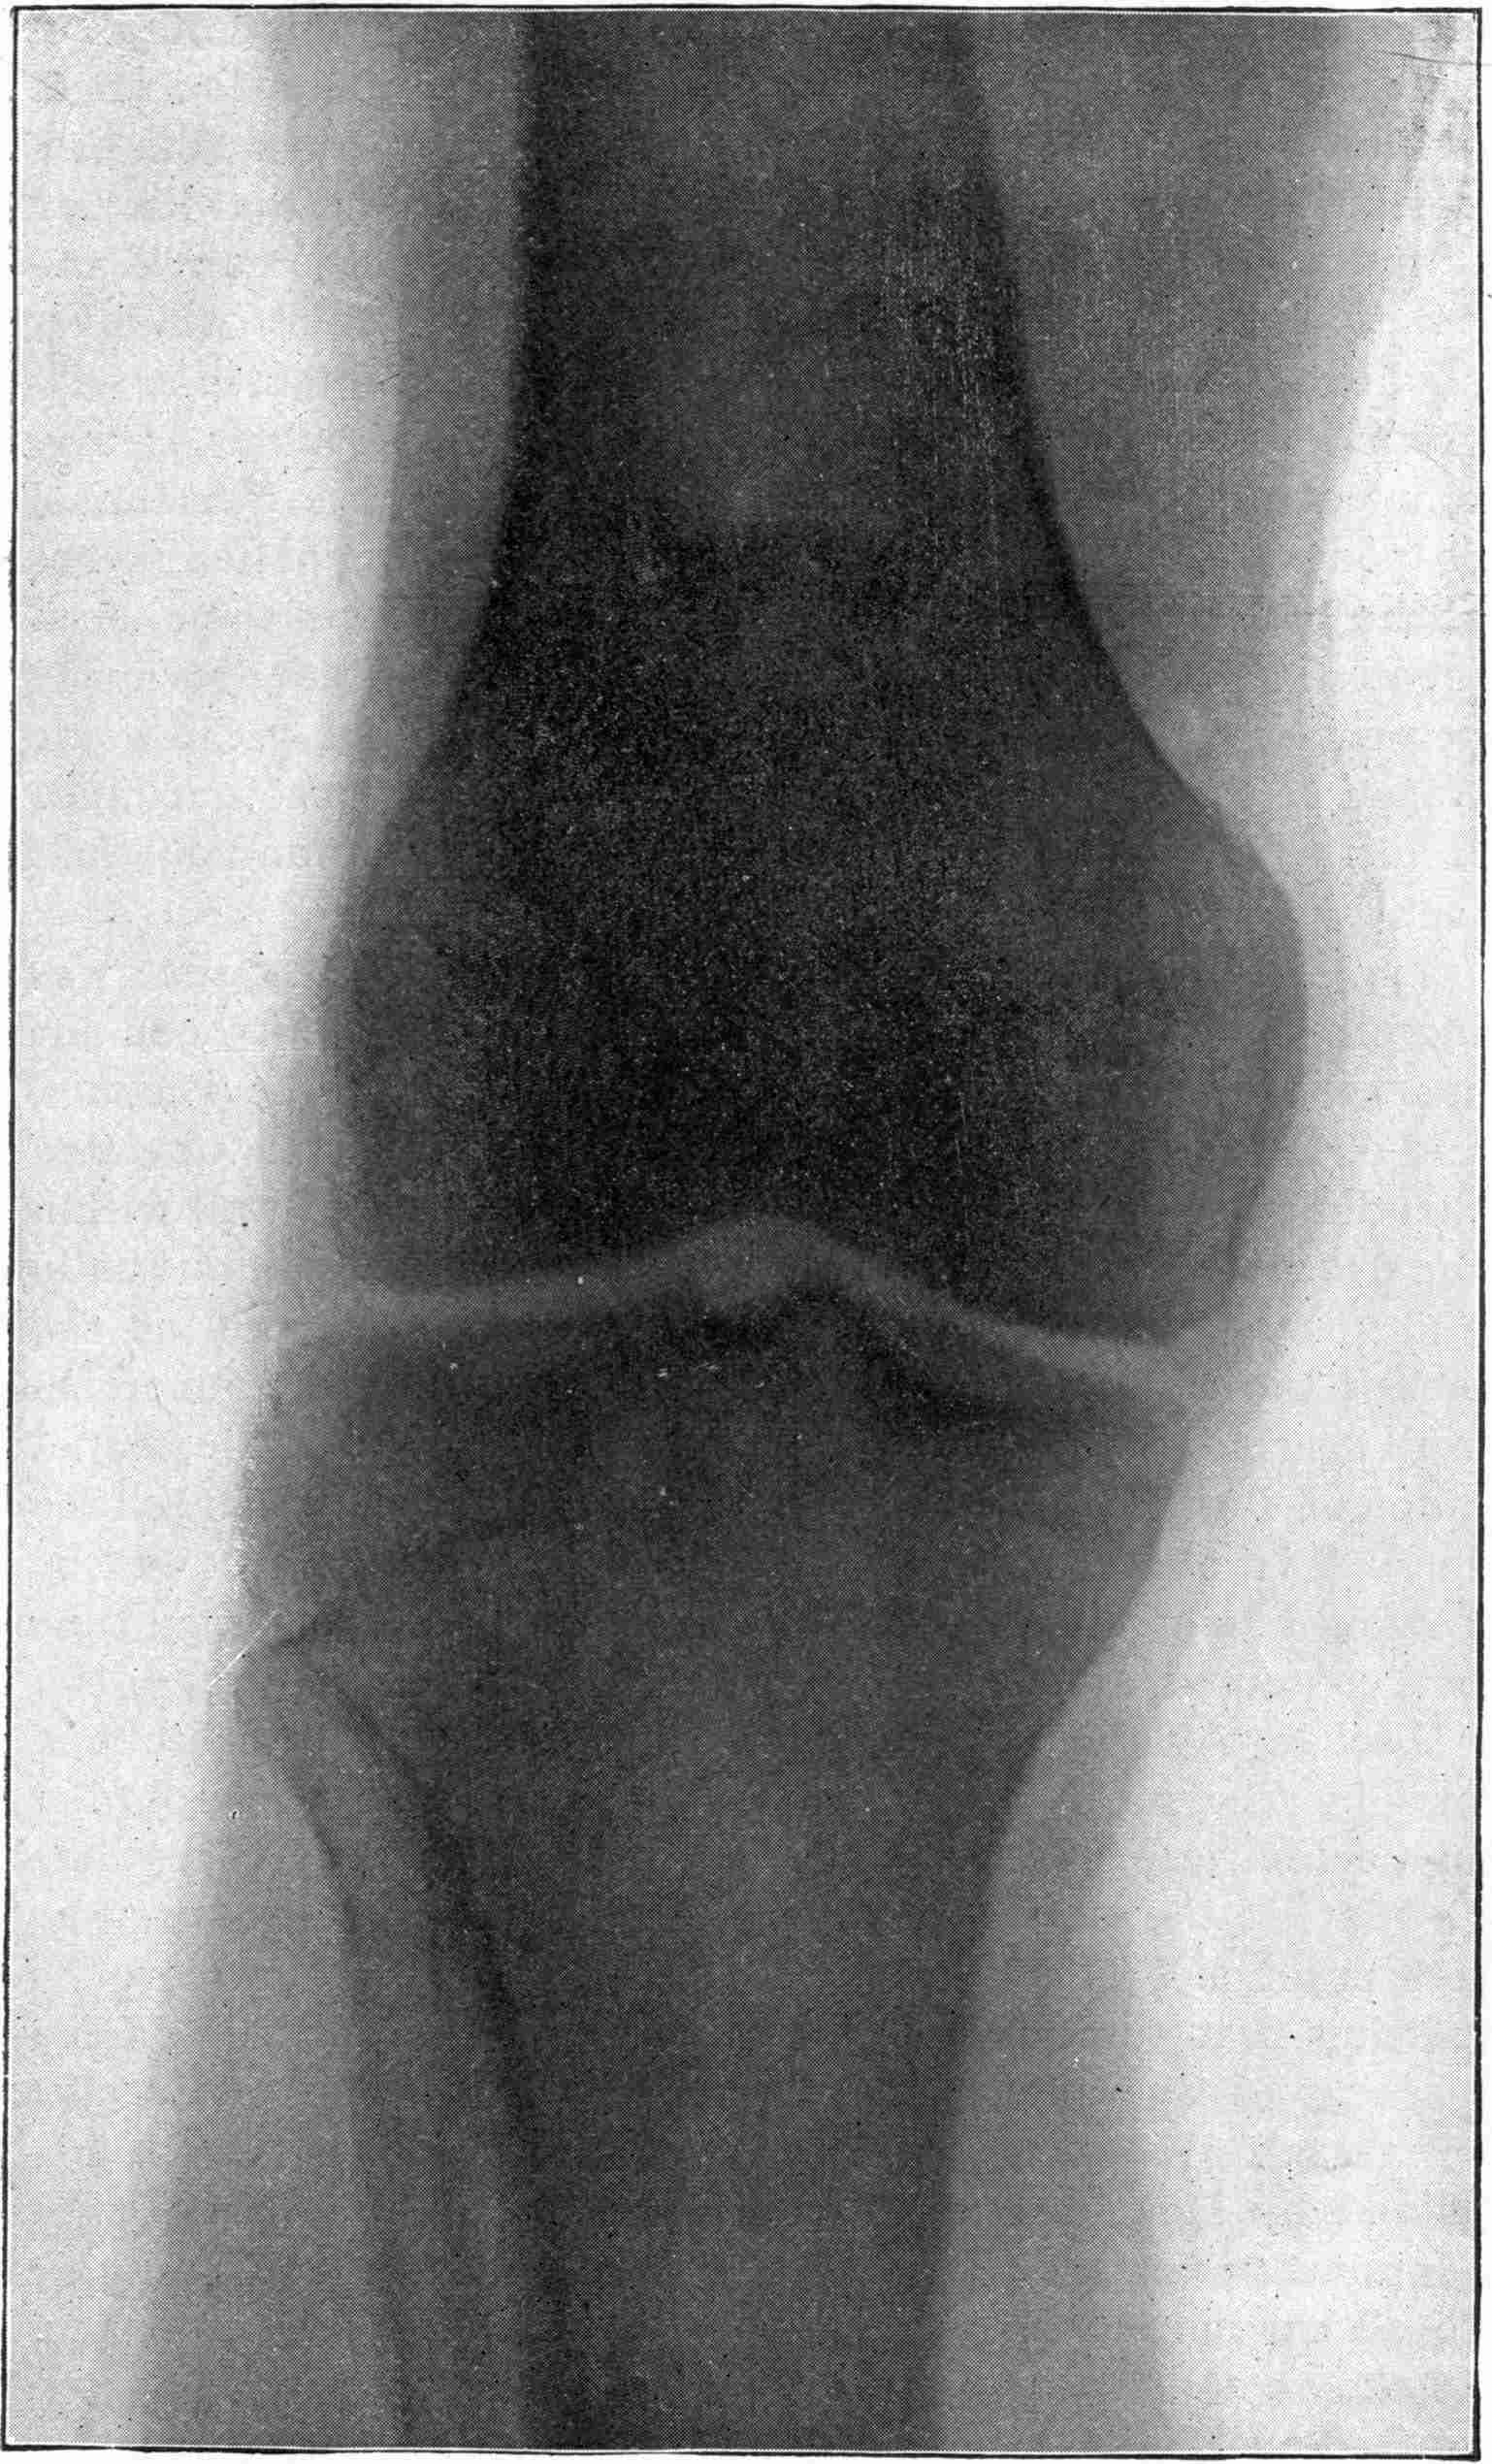

Fig. 1.—Head.

Fig. 2.—Broken Arm, Overlapping.

(Due to defective setting.)

Fig. 3.—Ribs.

Fig. 4.—Knee, Knickerbocker Buttons, Bullet in Femur.